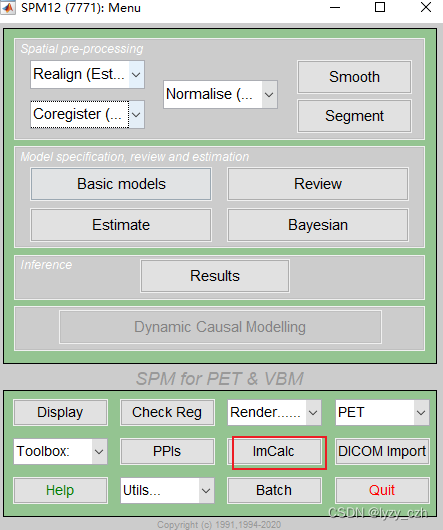

1) 打开matlab命令行输入spm pet,打开SMP12,界面如下

点击ImCalc

1、点击Batch